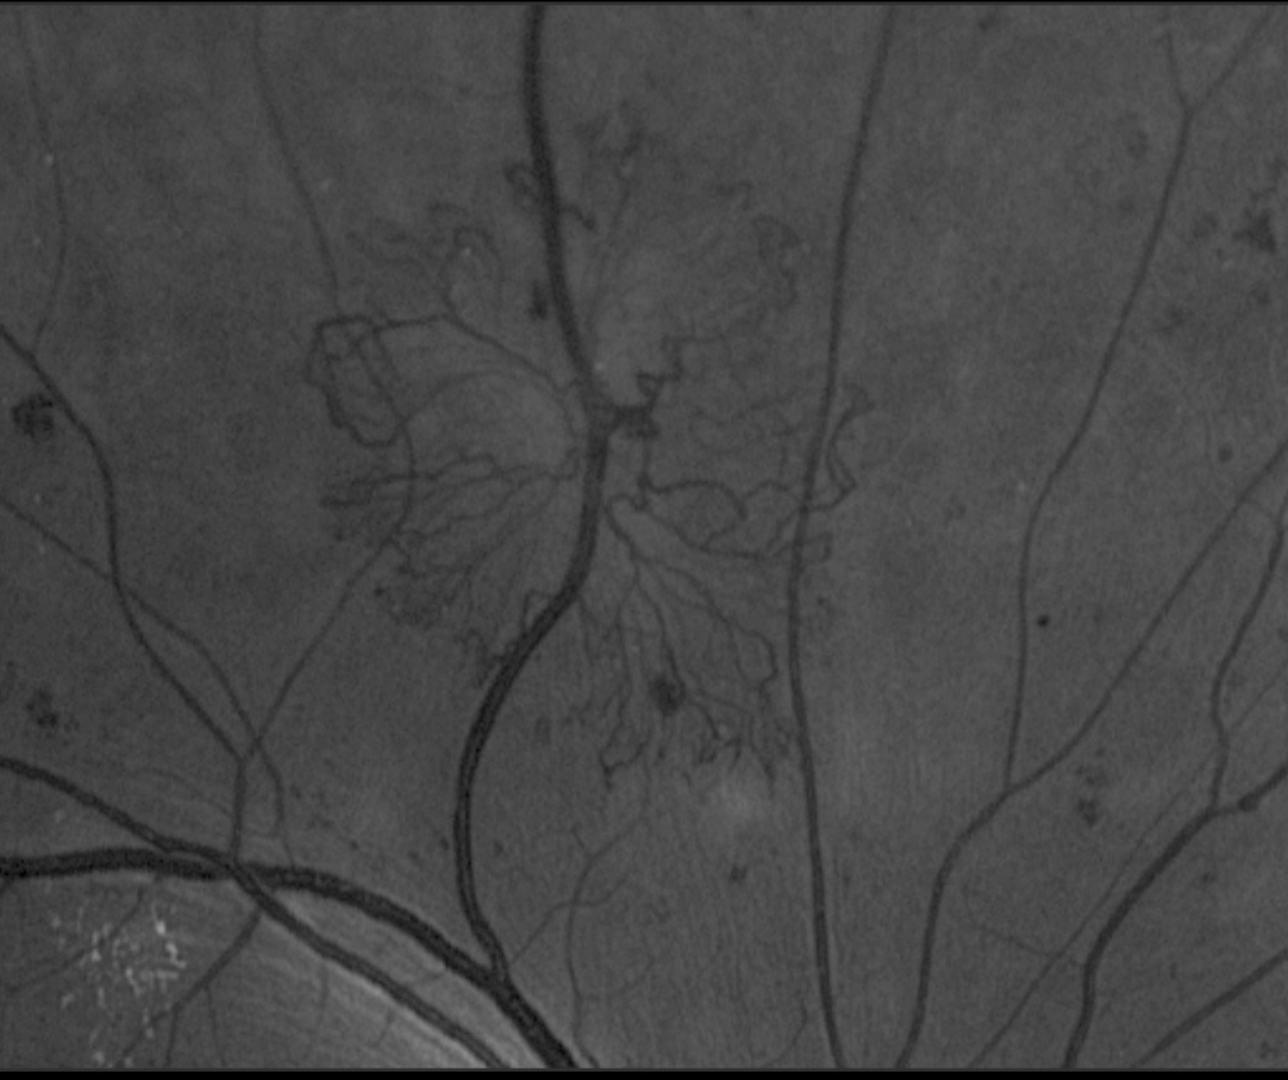

Initial visit: Optomap and green separation image (left eye)

More info

4 month follow-up: Optomap and green separation image (left eye)